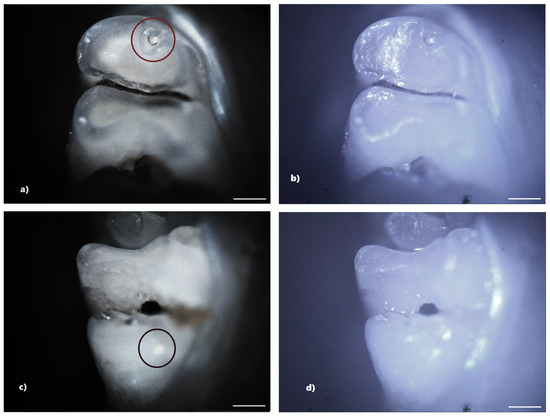

From the control group, five rats (33.33%) showed reduced demineralization in extent. Of these, three rats showed demineralization in the incisors, and two rats showed demineralization in the molars. No rats from the control group showed hypoplasia. Within this lot, out of a total number of 240 teeth, 10 teeth (4.17%), 4 incisors, and 6 molars showed demineralization. For each of the 10 affected teeth, the lesion was localized on a single surface, resulting in a total of 10 tooth surfaces with DDE (Figure 4).

Figure 4. Demineralization on the occlusal surface of 2 molars (a,c—PLM image, cross polarizers, 4× objective; b,d—BFM image, 4× objective). Scale bar represents 500 μm.